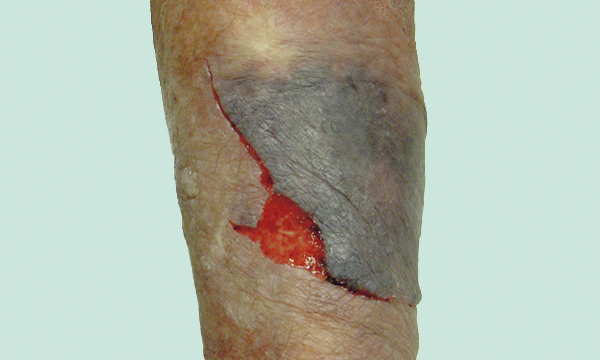

Skin tears are acute wounds caused by mechanical forces resulting in the separation of the skin’s outer layers. Skin tears are more likely to occur in vulnerable people such as older people and people with neurodegenerative conditions. Rising life expectancy means that the number of patients with skin tears is expected to increase. This article describes the characteristics of skin tears, details the risk factors for skin tears and explains the importance of using a holistic, evidence-based and person-centred approach to skin tear prevention, assessment and treatment. The article outlines the crucial role of nurses as part of the multidisciplinary team in the management of skin tears.